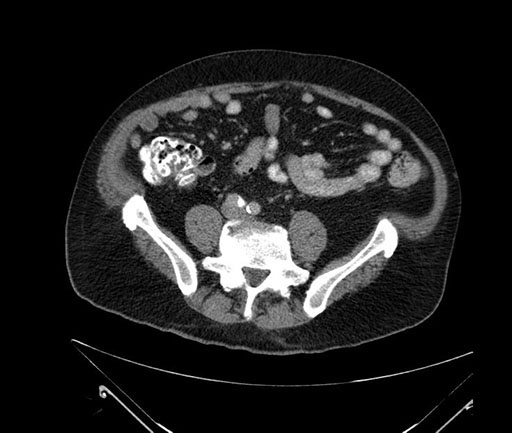

Whipple (pancreaticoduodenectomy) [case 7]

Imaging Analysis

Look through the patient's CT scan to identify any areas of concern for the necessary procedure.

Based on your CT findings, which issue(s) would give reason for "planned slowing down moment(s)" in this case?

Considering a standard Whipple procedure, what step(s) of the operation would you do differently in this case?